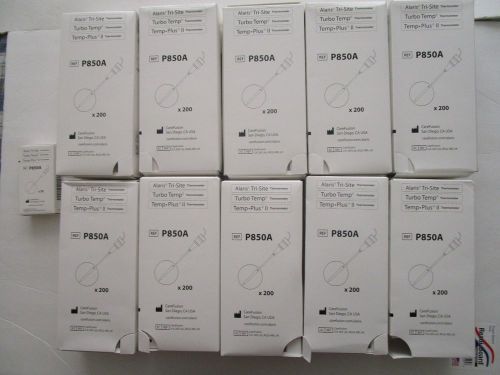

2000 ALARIS TRI-SITE TURBO TEMP TEMP PLUS II Thermometer Probes P850A CAREFUSION